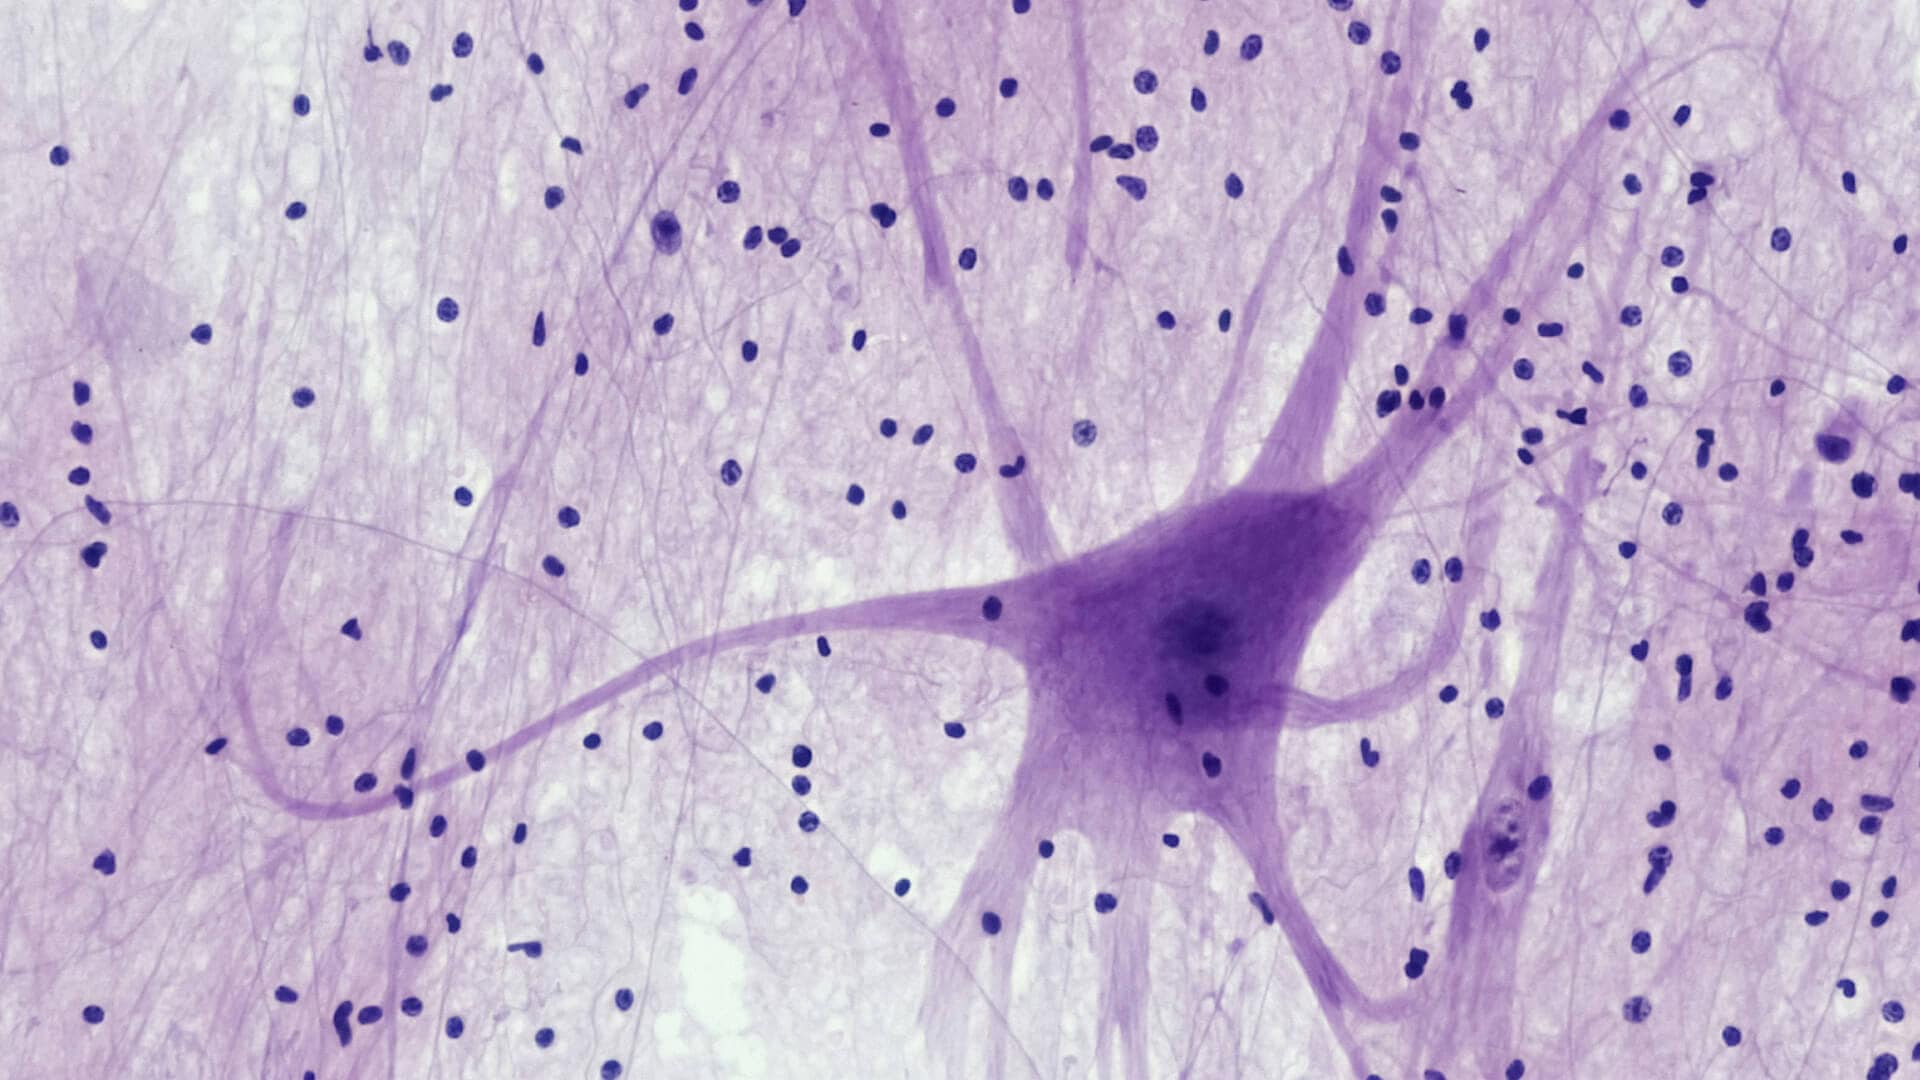

As a board-certified neuroradiologist with over two decades studying the brain, I can tell you this: being present in the moment is not simply a mindset. It is a biological state.

Your prefrontal cortex is engaged. Your cortisol rhythm is stable. Your nervous system is not braced in low-grade vigilance.